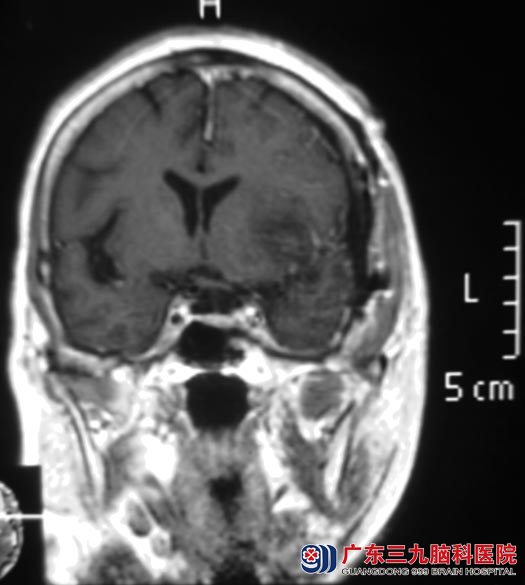

王奶奶今年76岁,一个月前开始出现头痛,以双侧额颞部明显,呈阵发性钝痛,偶有头晕。在当地医院行头颅CT检查,结果提示:左额叶占位,考虑肿瘤性病变,医生告知他们需要手术治疗。广东三九脑科医院头颅MR检查提示病变大小约21.6mm×23.6mm×23.8mm,考虑脑膜瘤。

心脏彩超检查提示:主动脉瓣退行性变并轻度返流,左室扩大;左室顺应性下降,经心内科专家会诊后,认为可以耐受手术。8月20日,由综合神经外科 鲁明主任主刀,在全麻下行左侧蝶骨嵴脑膜瘤切除术,术中见肿瘤基地部位于左侧蝶骨嵴,呈灰白色,质软,血供一般,与硬膜粘连紧密,予显微镜下小心分离,分块予肿瘤全切,手术顺利。经过一段时间的治疗,王奶奶没有出现任何并发症,顺利康复。病理结果为:脑膜皮细胞型脑膜瘤(WHO I级)。